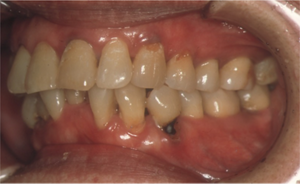

図8 器質的口腔ケアの効果(3か月後)

口腔ケアとしての介入により、認知機能(MMSE)の低下が抑制された。開始3か月目。基礎疾患(高血圧症・糖尿病)があるにもかかわらず、顕著な歯肉炎の改善がみられる。食欲も増し、笑顔も増加。口腔ケアの効果を施設職員と驚きをもって確認。